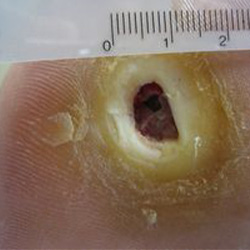

Before and After

Electrical Burn Injury